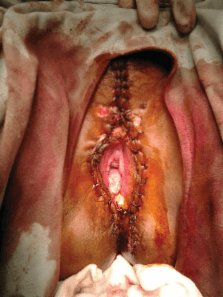

This condition are most commonly caused by which of the following serotypes of HPV

This condition is Genital Warts (condyloma accuminata)

Ans A

Ans. is ‘b’ i.e., Condyloma acuminata